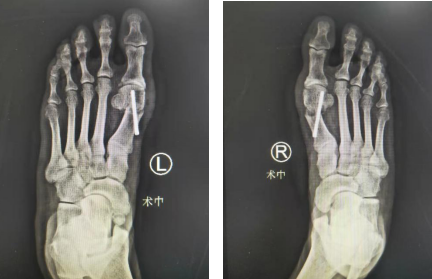

术前,张大妈双足负重位正侧位X线检查显示:双足拇外翻,双侧扁平足。

经术前充分准备,石荣剑、陈占斌、胡帆手术团队术中先行右足拇外翻微创截骨矫形术,取第1跖趾关节背外侧纵行切口长约2cm,使用微创专用勾刀松解肌腱,在第1跖骨头内侧取纵形切口长约1.5cm,切除踇囊、松解跖趾关节囊韧带,分离截骨线周围骨膜、“V形”截骨推移,进行内固定。同法处理左足拇外翻畸形,手术顺利,1个半小时就完成了双侧矫形。